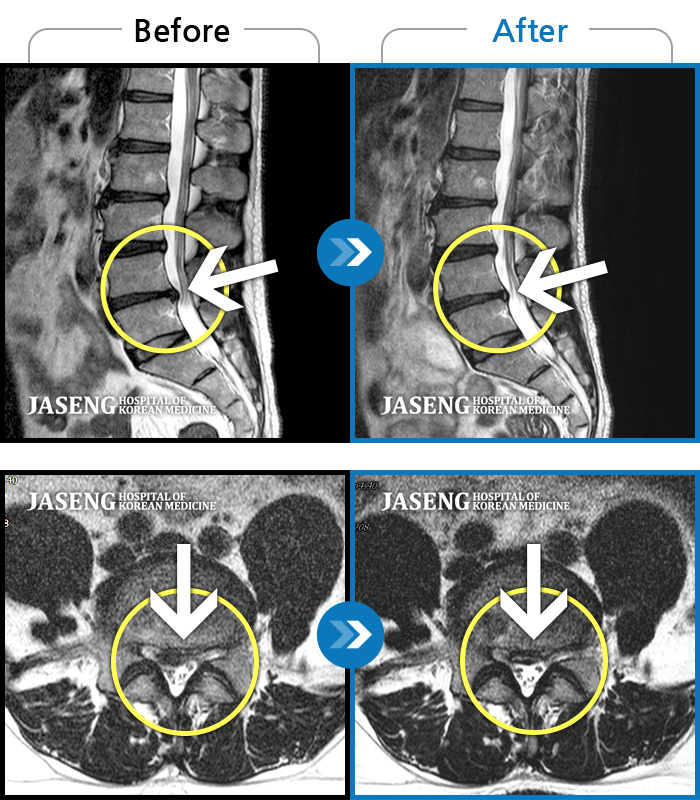

허리디스크

인천 · 강아현 원장

좌측 허리 통증 및 골반 통증이 심하여 걷는 것도 힘든 상태로 내원하셨습니다.

촬영시기

2024.05.08 ~ 2025.11.12

2025.11.14